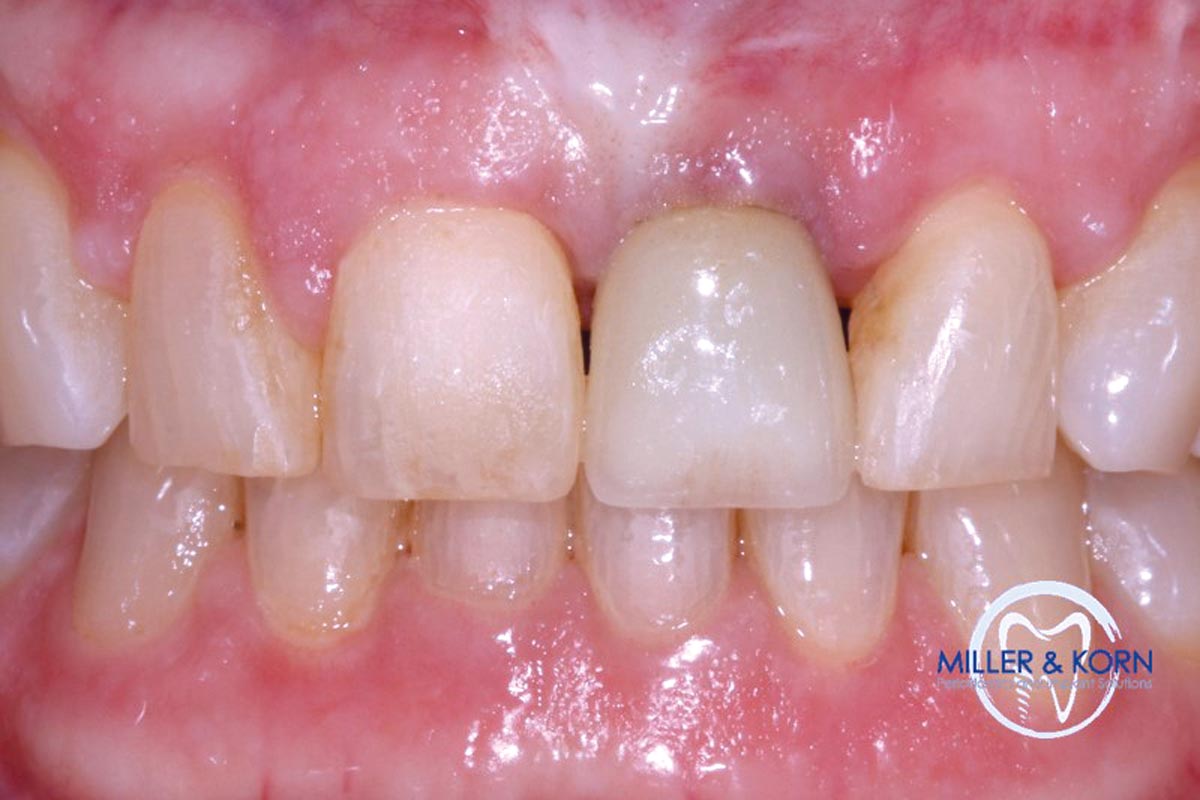

01/39 - The patient presented with pathologic mobility of upper left central incisor. Radiographic examination revealed significant circumferential attachment loss with an unfavorable crown to root ratio.Immediate implant placement and correction of horizontal and vertical bone loss using an allograft bone ring, cerabone® and Jason® membrane - Drs. Miller and Korn

The patient presented with pathologic mobility of upper left central incisor. Radiographic examination revealed significant circumferential attachment loss with an unfavorable crown to root ratio.